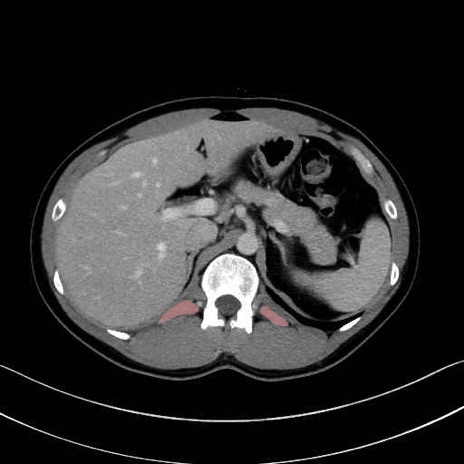

1. 体幹部(腹部・背部・後腹壁)の筋肉

腰方形筋 (Quadratus lumborum)

広背筋 (Latissimus dorsi)

脊柱起立筋 (Erector spinae)

多裂筋 (Multifidus)